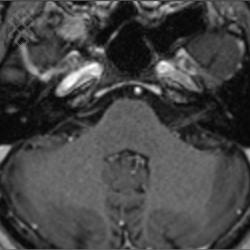

IRM des Conduits Auditifs Internes (CAI)

Pas d'indications